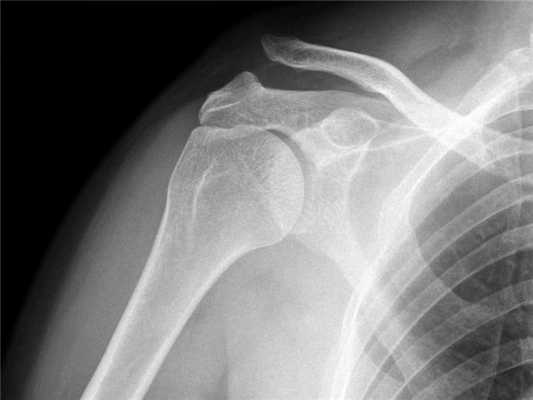

Данные по рентгену

При растяжении первого типа отсутствуют смещения на рентгене, при растяжении второго типа латеральный конец ключицы выше акромиона, но не смещен на 100%. При травме третьего типа субтотальный разрыв связок и 100% смещение на рентгене.

Диагноз вывиха акромиального конца ключицы

Диагноз вывиха акромиального конца ключицы иногда очень прост и все очевидно при осмотре, а иногда приходится решать целую головоломку. Наиболее оптимальным и распространенным способом диагностики является рентгенография. Стоит сказать, что, как не бывает одинаковых людей, так и не бывает одинаковых ключиц. Чаще всего причиной ложного диагноза индивидуальные особенности акромиально-ключичного сустава.

Поэтому целесообразно выполнять рентгенограмму не одного плеча, а двух сразу - что позволит оценить нормальное строение противоположной ключицы.

В сомнительных случаях иногда выполняют функциональную рентгенографию - в руку берут груз, который оттягивает ее вниз и вывих становится более очевидным.

Для подстверждения диагноза выполняется рентгенография плечевого сустава. На рентгенограмме четко видно, если произошел вывих акромиального конца ключицы.

Для постановки диагноза и для определения степени повреждения акромиально-ключичного сочленения наиболее информативным методом исследования является рентген.

На рентгене при первой степени разрыва акромиально-ключичного сочленения будет видно расхождение между ключицей и акромионом.

При второй степени мы видим выступание ключицы над акромионом на расстояние не более половины ее диаметра.

При третьей степени ключица выступает над лопаткой на полный свой диаметр и даже более того.

Рис. 1- Разрыв акромиально-ключичного сочленения.

Наиболее распространенная причина вывиха акромиально-ключичного сочленения - это прямое падение на плечо . При таком падении повреждаются связки, окружающие и стабилизирующие акромиально-ключичное сочленение.

Если удар достаточно сильный, происходит разрыв связок, отходящих от нижней стороны ключицы. Это вызывает "разъединение" ключицы и лопатки (рис.1). Лопатка смещается вниз под весом руки, в результате чего появляется "шишка", или бугорок, над плечом.

- Легкий вывих плеча приводит к растяжению связок акромиально-ключичного сочленения без смещения ключицы и на рентгеновском снимке выглядит нормально.

- При более серьезном повреждении происходит разрыв связок акромиально-ключичного сочленения и растяжение или небольшой надрыв клювовидно-ключичной связки со смещением ключицы.

- В наиболее серьезных случаях при вывихе плеча происходит полный разрыв как связок акромиально-ключичного сочленения, так и клювовидно-ключичной связки, в результате чего акромиально-ключичное сочленение сильно деформируется.

Данную травму легко диагностировать, если происходит деформация (смещение). Если деформация невыраженная, диагностировать повреждение врачу помогает локализация боли и рентгеновский снимок. Иногда наличие груза в руке у пациента усиливает смещение, что помогает лучше увидеть повреждение на рентгеновском снимке.